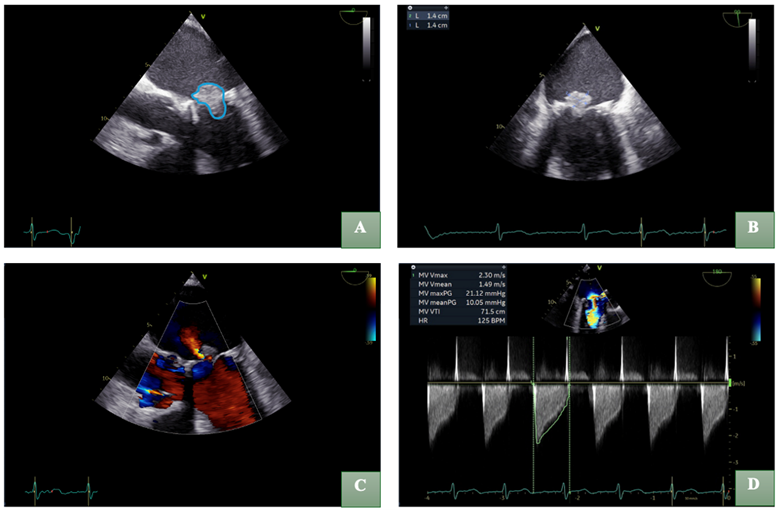

Given the increased risk of infective endocarditis, a transthoracic echocardiography was performed, revealing a preserved left ventricular ejection fraction of 50% and a mobile mass attached to the mitral valve (Figure 2). Transesophageal echocardiography (TOE) confirmed a 1.4x1.4cm vegetation causing significant stenosis (mean pressure gradient 10mmHg) and mild valvular regurgitation (Figure 3).

Figure 3: Transesophageal echocardiography (TOE) confirmed a vegetation, delineated by a blue outline (A) with dimensions measuring 1.4x1.4cm on magnified imaging (B) resulting in significant mitral stenosis and mild valvular regurgitation (C). Mitral valve maximal velocity (MV Vmax) 2.30 m/s; Mitral valve mean velocity (MV Vmean) 1.49 m/s; Mitral valve maximal pressure (MV max PG) 21.12 mmHg; Mitral valve mean pressure gradient (MV mean PG) 10.05 mmHg; Mitral valve velocity time integral (MV VTI) 71.5cm; Heart rate (HR) 125 beats per minute (D).